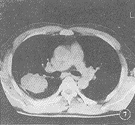

18例CT图像显示病灶呈明确的软组织块影,12例瘤体内有小空洞(图5),空洞内CT值为气体密度,8例在肿块的周围有炎性渗出(图6),4例瘤体边缘呈分叶状(图7),7例在肿块边缘具有长毛刺影(图8),9例在假瘤的附近可见局限性胸膜增厚,形成幕状,线状粘连带。

图6 左肺块影周围呈炎性渗出表现

CT图像把假瘤与肺的境界面显示得非常清楚,即使胸片表现为大片状或团块状模糊影,但在CT图像上则表现为境界清楚的块影[3]。本组30例胸部平片仅1例发现空洞,而18例CT扫描就有12例显示小空洞存在,这种小空洞可以单发,也可以多发。除此以外,CT图像上显示肿块周围长毛刺,胸膜增厚,粘连征像对本病诊断有着重要意义[3~7]。